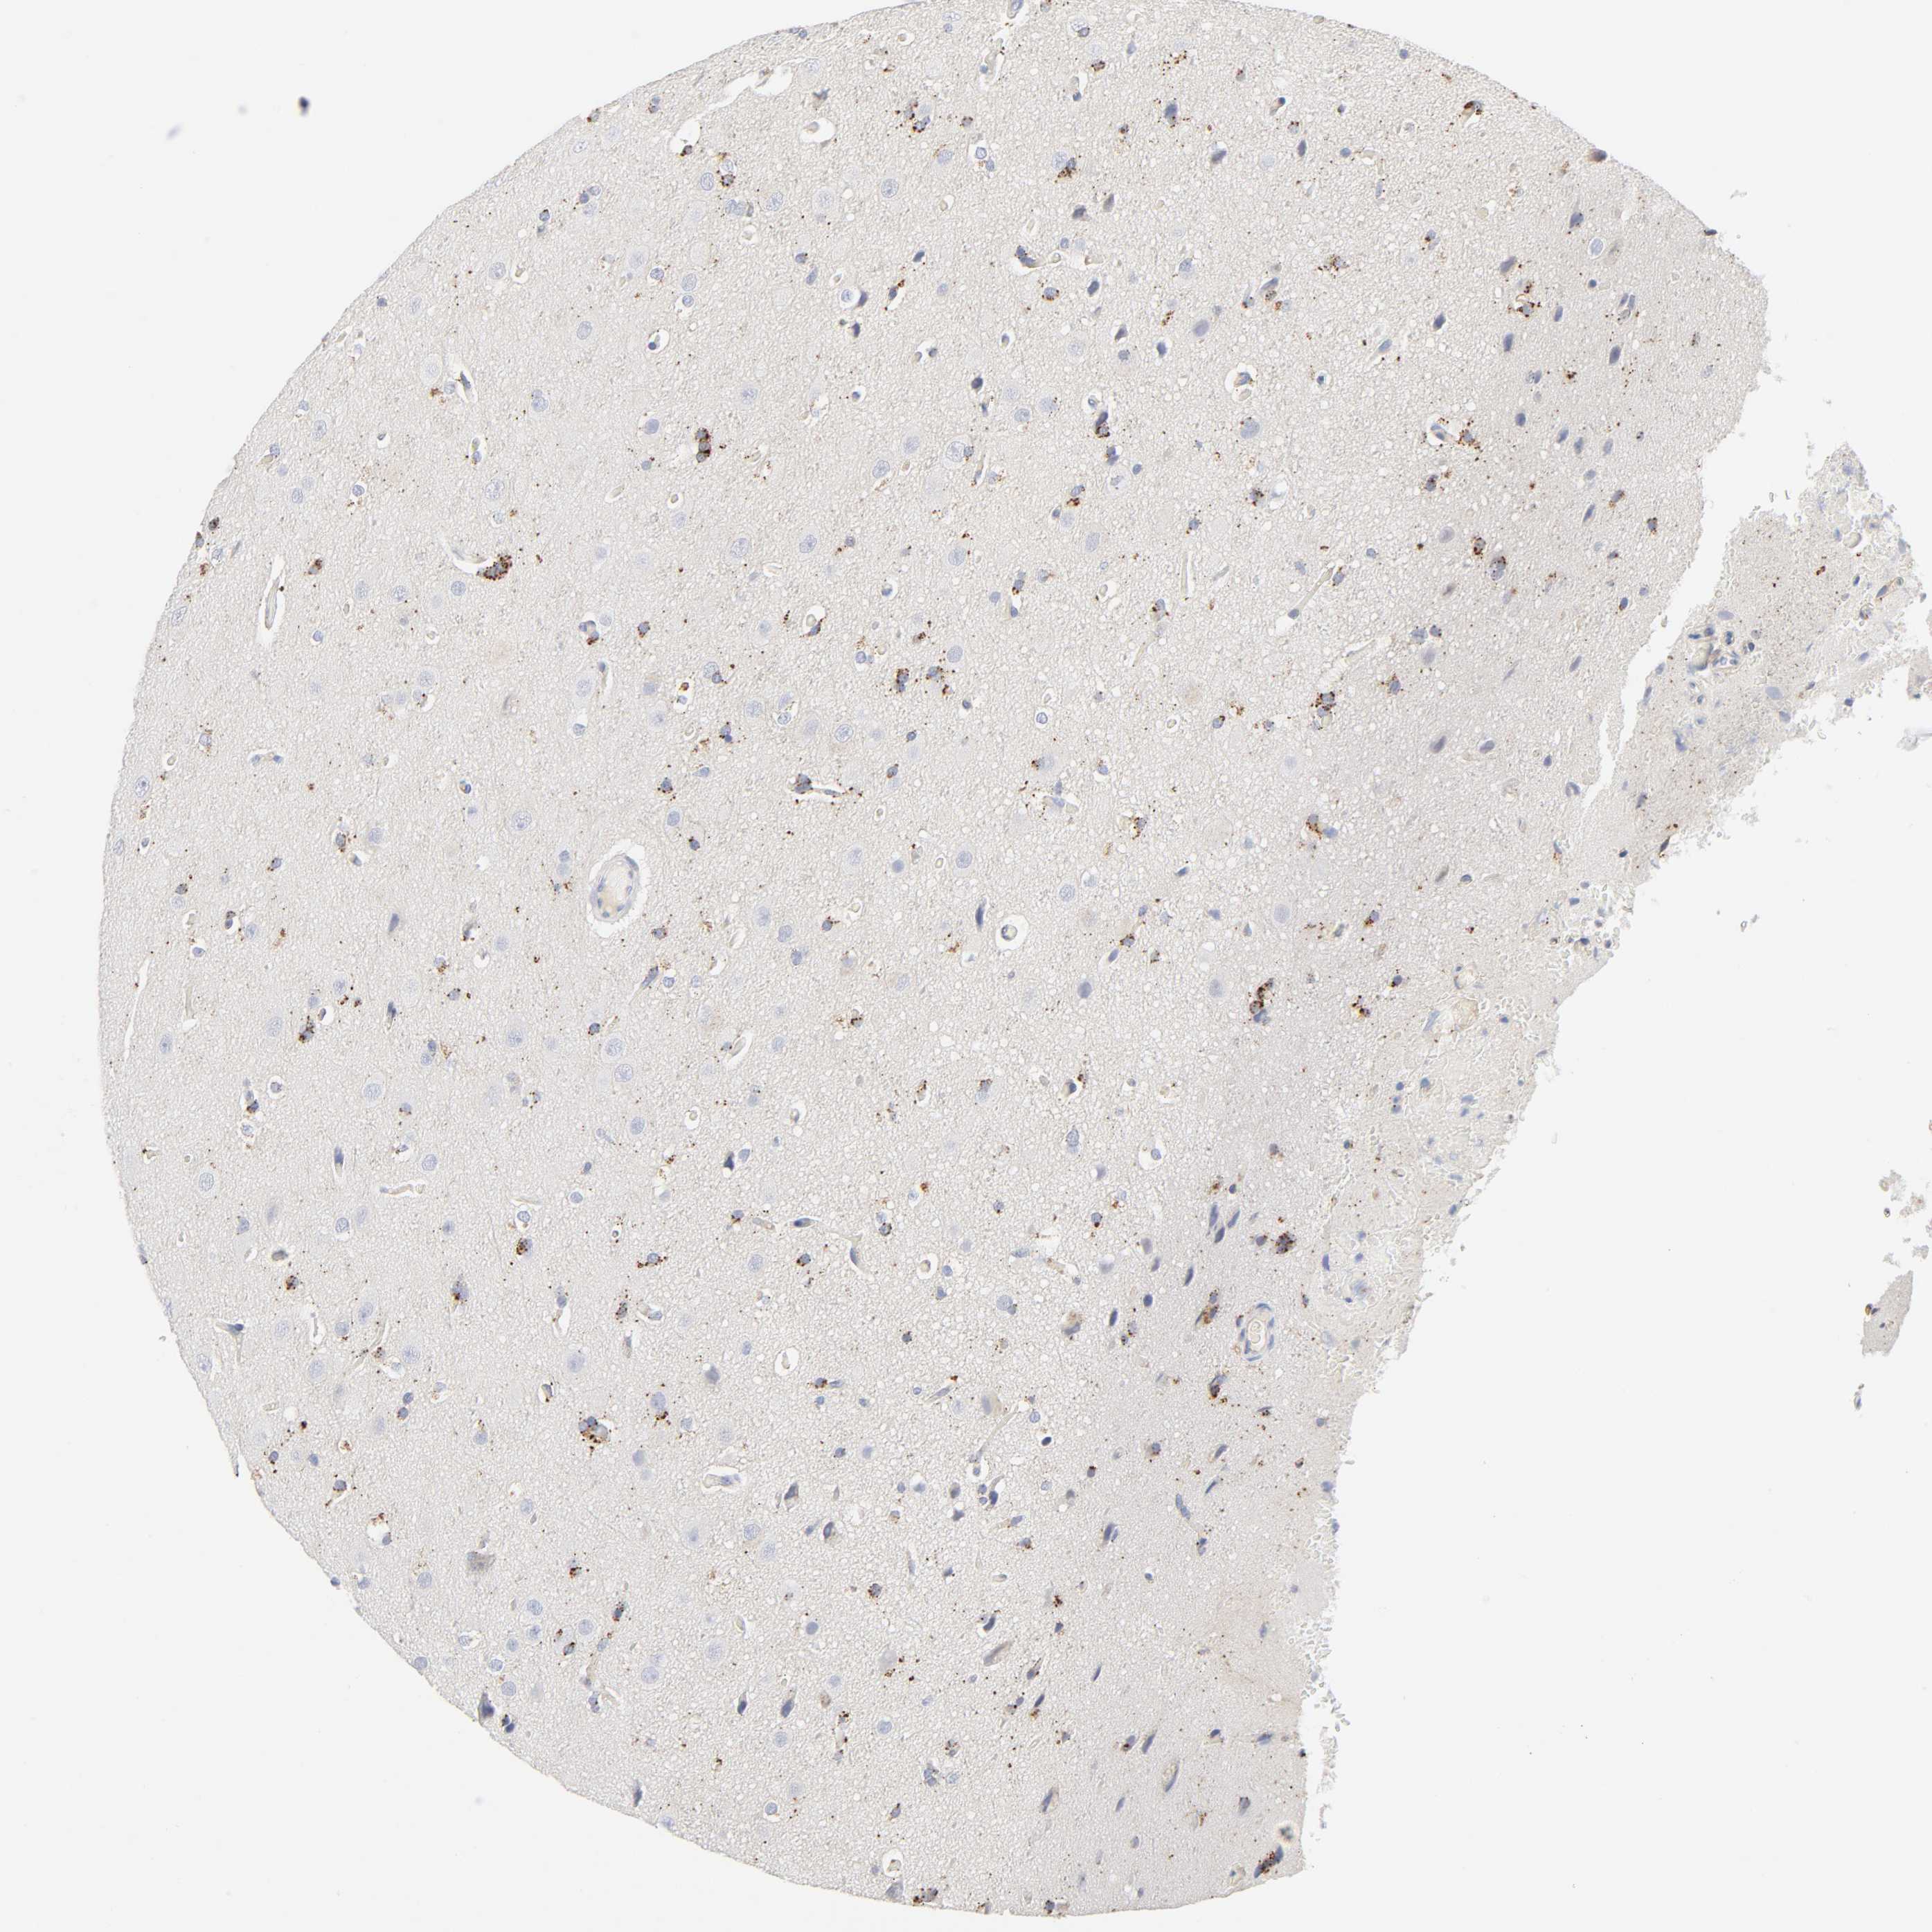

GLIOMA - Protein expressioni

A mouse-over function shows sample information and annotation data. Click on an image to view it in a full screen mode. Samples can be filtered based on level of antibody staining by selecting one or several of the following categories: high, medium, low and not detected. The assay and annotation is described here.

Note that samples used for immunohistochemistry by the Human Protein Atlas do not correspond to samples in the TCGA dataset.

Antibody stainingi

Antibody staining in the annotated cell types in the current human tissue is reported as not detected, low, medium, or high, based on conventional immunohistochemistry profiling in selected tissues. This score is based on the combination of the staining intensity and fraction of stained cells.

Each image is clickable and will lead to virtual microscopy that enables deeper exploration of all samples and also displays staining intensity scores, fraction scores and subcellular localization as well as patient and tissue information for each sample.

Antibody HPA003756

Staining

High

Medium

Low

Not detected

Intensity

Strong

Moderate

Weak

Negative

Quantity

>75%

75%-25%

<25%

None

Location

Nuclear

Cytoplasmic/membranous

Cytoplasmic/membranous,nuclear

Glioma, malignant, High grade

Glioma, malignant, Low grade

Glioma, malignant, NOS